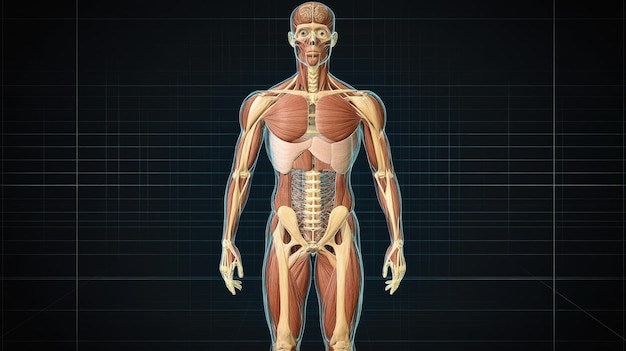

Human Anatomy Detailed 3D Model Of Male Muscular S 411059118

14/11/2025

ร่างกายมนุษย์